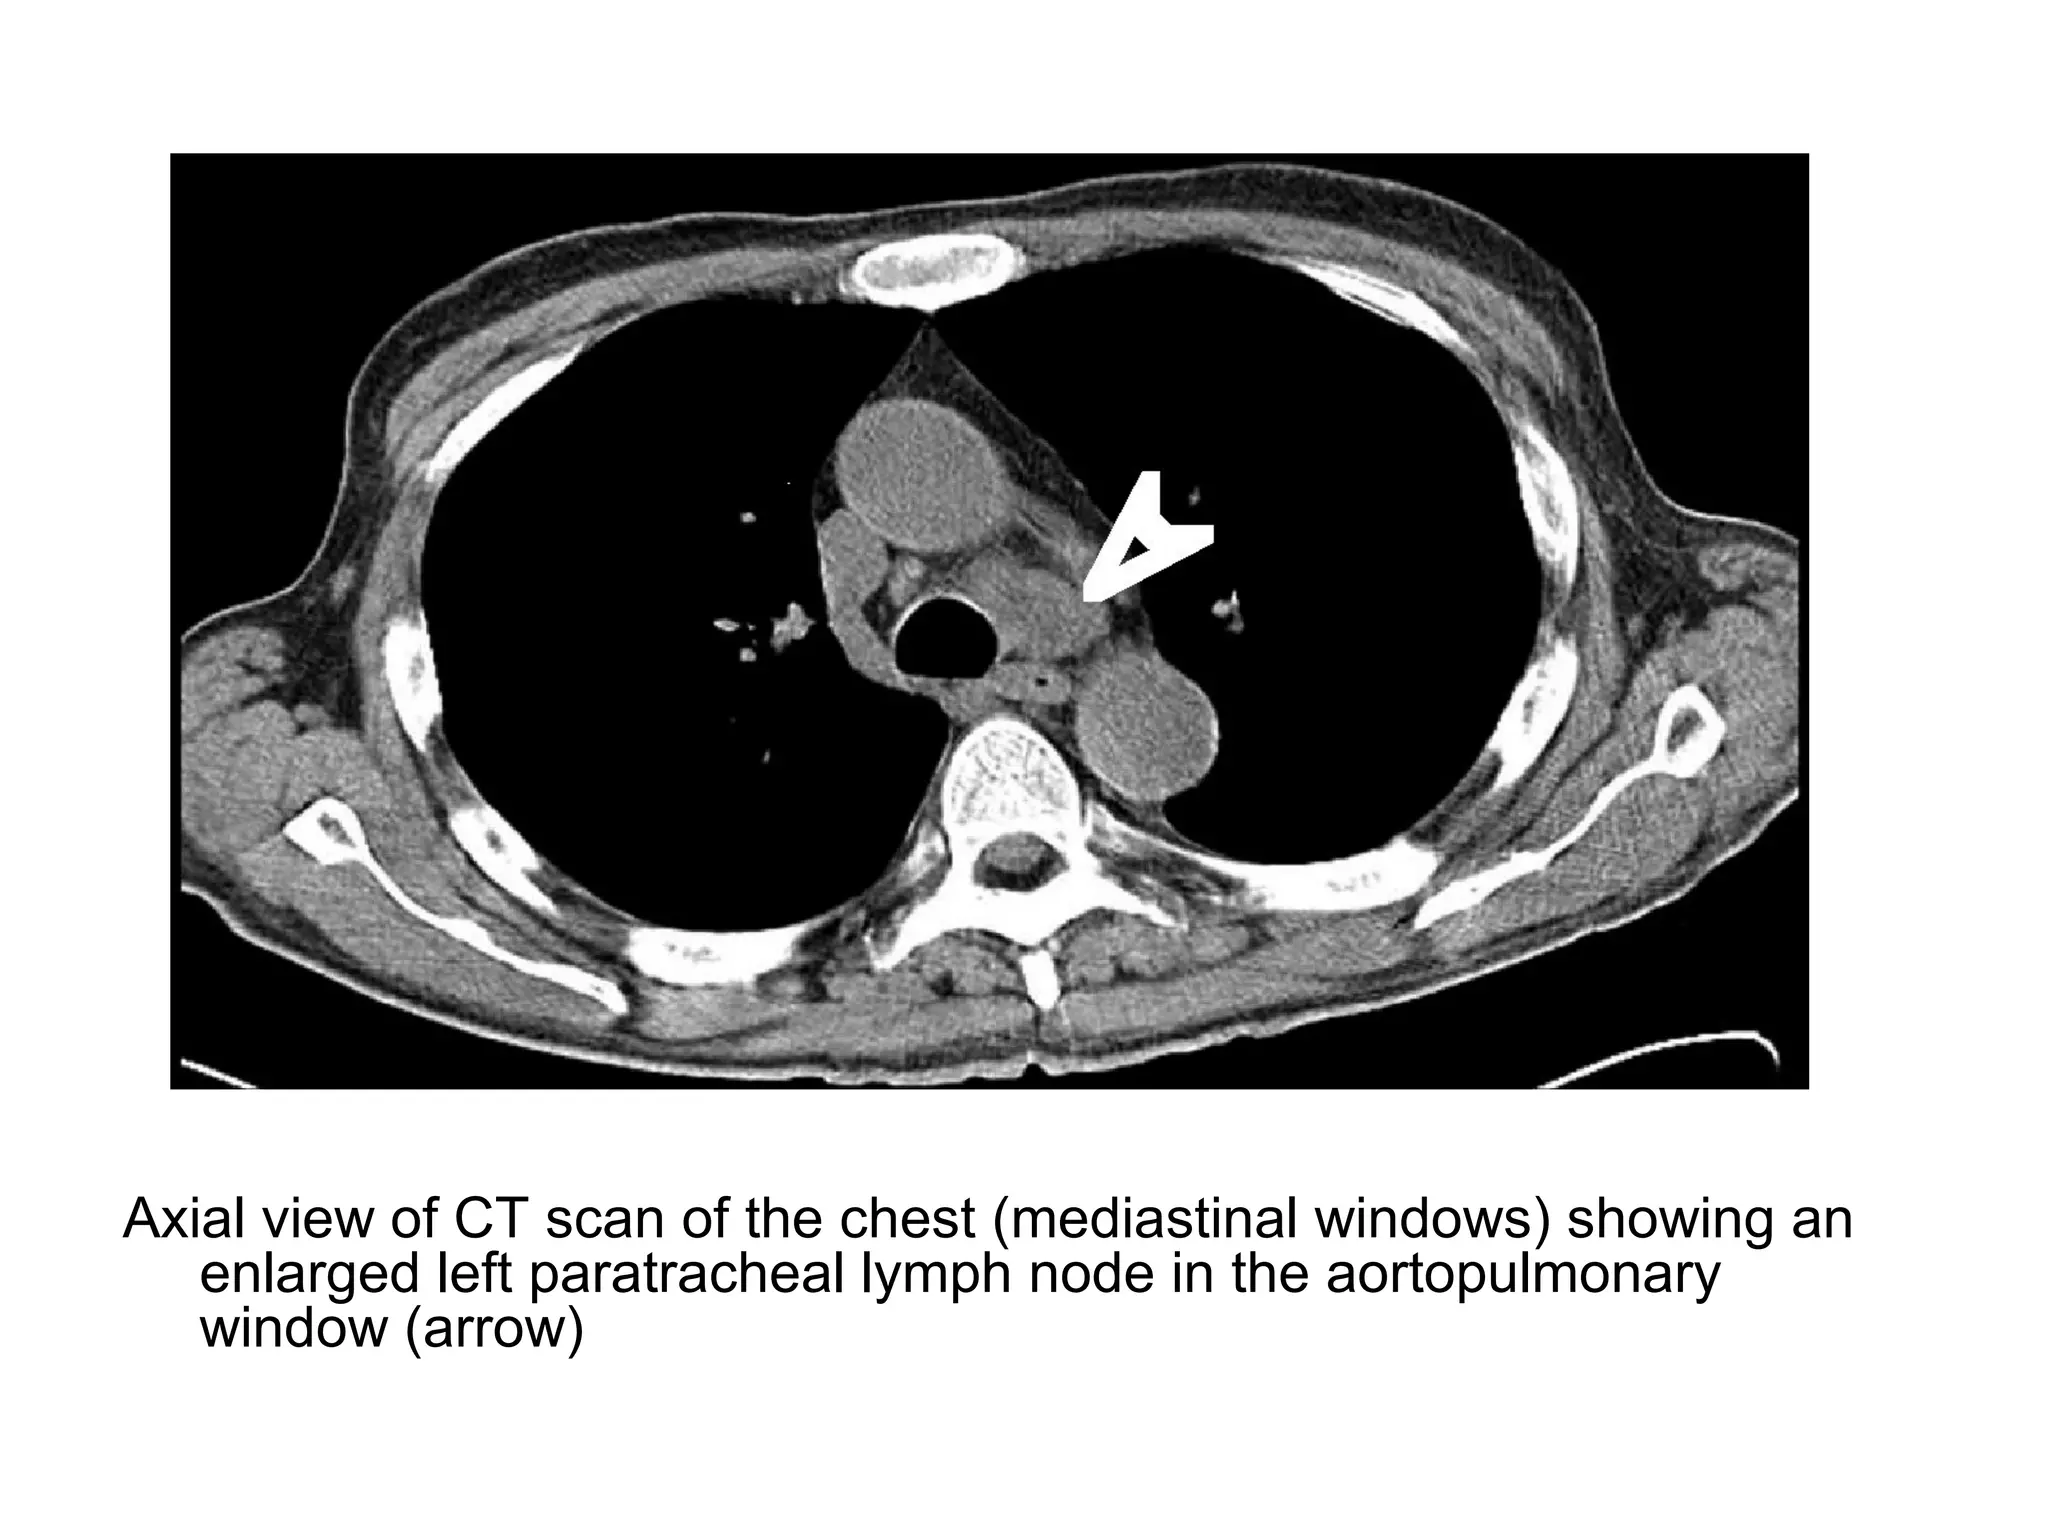

Axial view of CT scan of the chest (mediastinal windows) showing an

enlarged left paratracheal lymph node in the aortopulmonary

window (arrow)